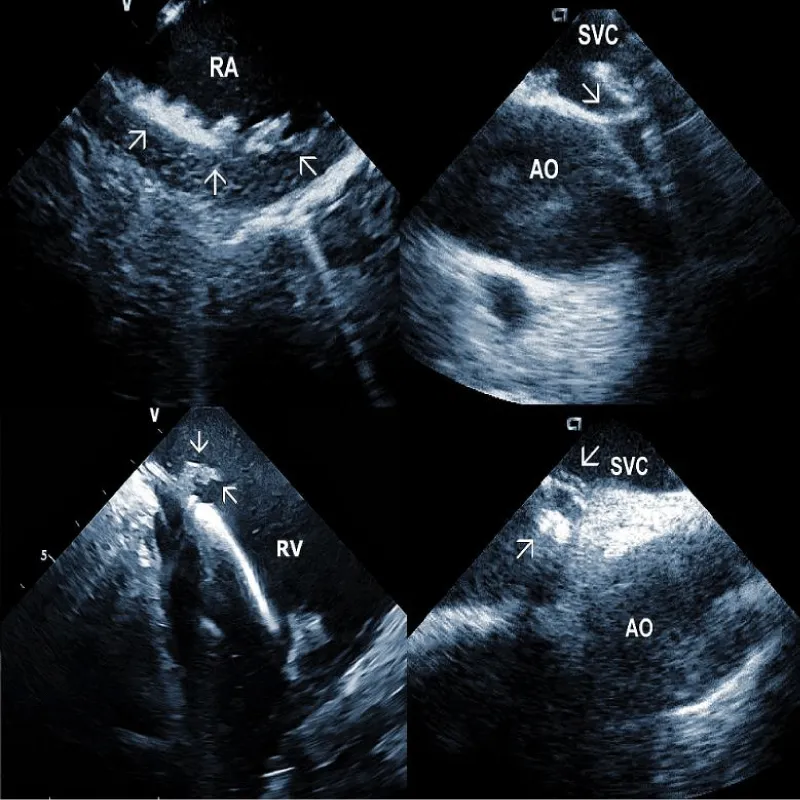

Areas of fibrous adherence: Areas of fibrous adherences or attachments (i.e., scar tissue) can be visualized as echo-dense structures along the lead course (Figure 3A). Multiple leads are usually attached by fibrous tissue together (Figure 3B). The location of fibrous adherence can be anywhere in the course of the lead [7,10]. In a study by Bongiorni, et al. [7], scar tissue was noted by ICE in the subclavian vein, innominate vein, and the right ventricle in about 80%, 68%, and 68% of cases, respectively. Sadek, et al. [10] described attachments less frequently – only in 18/50 pts (36%), predominantly intracardiac. Anecdotal cases were reported on specific locations of adhesions, such as a vulnerable “stalk” attaching the papillary muscle to the RV endocardium [18]. Notably, the fibrous attachment presence correlated with the extraction procedure’s difficulty. These patients were more likely to have a “complex” extraction procedure. Subjects who did not have evidence of lead attachment were less likely to require the advancement of the extraction sheaths past the superior vena cava and less likely to require advanced extraction tools such as snares.

Figure 3A: Fibrous adherences (arrow) attaching the lead within the superior vena cava (SVC). AO: Ascending aorta.

Figure 3B: A convolute of 2 leads attached together with fibrous tissue at the level of tricuspid valve (arrows). RA: Right Atrium; RV: Right Ventricle.

Residuals after TLE: Residual fibrotic tissue after TLE, called ghosts, has been described as a new phenomenon in cardiology (Figure 4). The presence of ghosts was first described by Rizzello, et al. using ICE [22]. Caiati, et al. studied a cohort of 40 patients using ICE before and after TLE to document the relationship between thrombotic or fibrotic reactions to the lead and with subsequent occurrence of ghosts [23]. ICE could identify thickened lead (thickness ≥ 1 mm than the vendor declared thickness in at least one lead) and fibrotic attachment to the cardiac wall in a substantial number of subjects. Thickening was noted in 25/40 patients (62%) overall, involving the atrial (2 patients (5%)) or the ventricular (9 patients (22.5%)) or both leads (14 patients (35%)). The fibrotic attachment was observed in 12/40 patients (30%). Both thickening and fibrotic attachments were significantly associated with subsequent ghosts (p < 0.001 and p = 0.002, respectively), but lead thickening had a higher prediction power. Narducci, et al. demonstrated that the presence of ghosts could be associated with a worse prognosis in device-related infective endocarditis [24]. Analyzing 217 TLE cases, the authors identified ghosts in 30 (14%) patients after TLE. In their study, endocarditis was one of the independent predictors of the presence of ghosts. Poterala, et al. detected ghosts after TLE in 19% of cases [25]. These residual fibrotic tissues were most often located along the originally implanted lead’s route. The local infection and infective endocarditis were associated with a larger number of ghosts after the removal procedure (p = 0.006). Besides frequent association with infection, detection of ghosts after TLE is also important for other reasons. Otherwise, they can be mistakenly interpreted in the echocardiographic examination as new pathological structures of unknown origin. In such a situation, the patient can be subject to unnecessary anticoagulant therapy, invasive diagnostic procedures, and/or cardiac surgery. Given the potential risks of ghosts, their presence should probably be noted on post-extraction imaging and might warrant closer post-extraction follow-up [4].

Figure 4: Ghosts within the superior vena cava (SVC) after removal of the ICD leads marked by arrows. AO: Aorta.

Additional echocardiographic findings: ICE can detect less frequent but important abnormalities, which may relate to TLE or subsequent lead implant. An example could be complete obstruction of the superior vena cava or the brachiocephalic vein. An additional curious finding which can be observed by ICE, is the deformation of the right ventricle during traction on the lead, often leading to hypotension [30]. The ability to visualize the lead-tissue interface during extraction (Figure 5B) and assess lead binding sites allows the operator to continuously evaluate the response to extraction maneuvers. Monitoring the progression and alignment of the laser extraction sheath with the lead is another potential utility of ICE (Figure 5C).

Figure 5B: Traction on the RV wall at the site of attachment of the ICD lead (arrow).

Figure 5C: Progression of the laser sheath (arrow) over the lead in the superior vena cava (SVC). Artifacts at the bottom are caused by application of laser beam.

Representative Figure: Illustrative examples of clinical utility of intracardiac echocardiography in transvenous lead extraction.